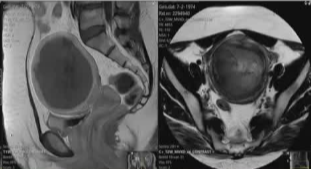

基于术前的磁共振成像特征以及血管造影信息

术前 |

术后 |

双侧子宫动脉栓塞,右侧1安瓶 500-700μ吗,左侧4安瓶500-700μm +7安瓶 700-900μm 可吸收微球 |